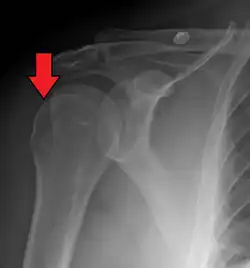

| Anterior shoulder dislocation on X-ray with a large Hill–Sachs lesion | |

A Hill–Sachs lesion, or Hill–Sachs fracture, is a cortical depression in the posterolateral head of the humerus. It results from forceful impaction of the humeral head against the anteroinferior glenoid rim when the shoulder is dislocated anteriorly.